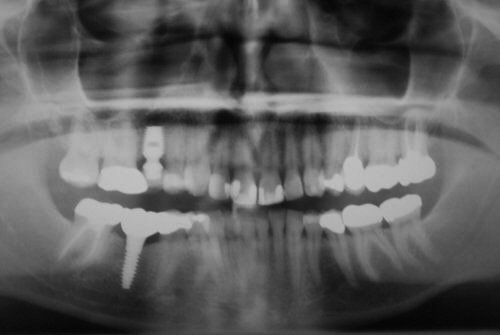

Unfortunately, it can be the case that a tooth (or teeth) are so badly damaged by trauma, bacteria, or tooth decay that removal is the only option. In this case, we recommend that a patient has dental implants inserted to replace any missing teeth. Modern dental implants are long lasting, strong, and look, feel, and function just like real teeth.

At the Dental Innovations clinic in Wasilla, AK, we specialize in single and multiple implant restorations. Our team can use a wide range of implant systems to provide patients with a full mouth of even, strong teeth. Contact our dental clinic today to arrange a consultation to discuss what dental implants may be the best for you.